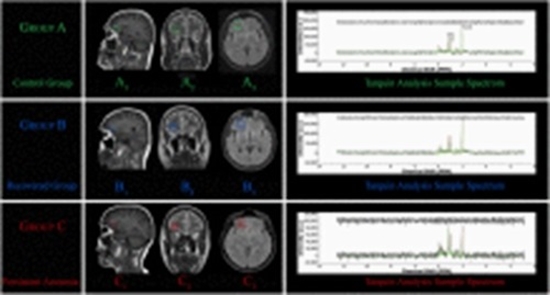

Methods: In a new categorization, 54 subjects were studied as two major groups of COVID-19-related anosmia and normal each of which includes 27 subjects. Iran Recognition-Smell Identification Test (IR-SIT) over a three-month follow-up period was utilized for olfactory function assessment and anosmia diagnosis. Proton Magnetic Resonance Spectroscopy (1H-MRS) was employed to examine changes of metabolites in OFC, including N-acetyl aspartate (NAA), choline (Cho), and creatine (Cr), as well as their ratios. Additionally, a linear regression was applied to investigate the potential correlation between MRS data and IR-SIT scores.

Results: Patients with COVID-19-induced anosmia exhibited a significant reduction in NAA, Cho, and Cr levels in the OFC region compared to the control group. Moreover, NAA/Cho and NAA/Cr ratios were lower in the anosmia patients, whereas the Cho/Cr ratio elevated. The NAA/Cho ratio had the highest linear correlation with IR-SIT scores in anosmia.